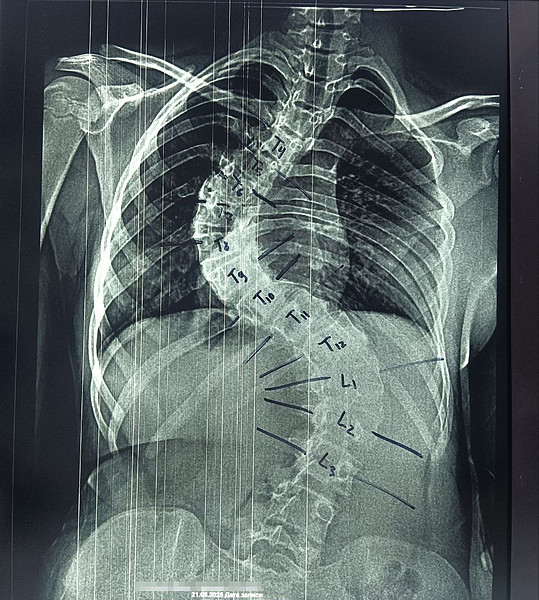

< < <19102022-30photo_2025-08-23_12-17-55До_ОперацияПосле> > >

До_.